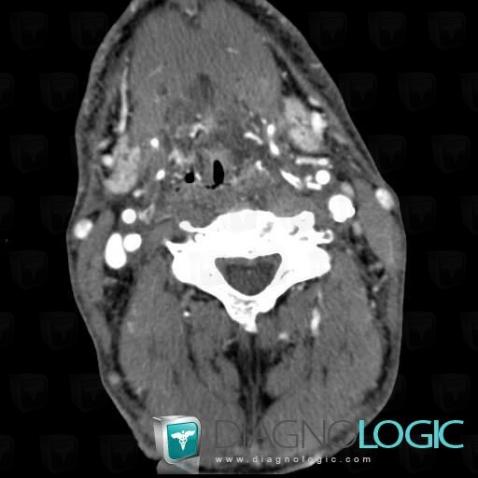

Postradiation edema, Larynx, CT

Here is the specific information in the key image above:

- Diagnosis Postradiation edema, Location(s) Larynx, with gamuts